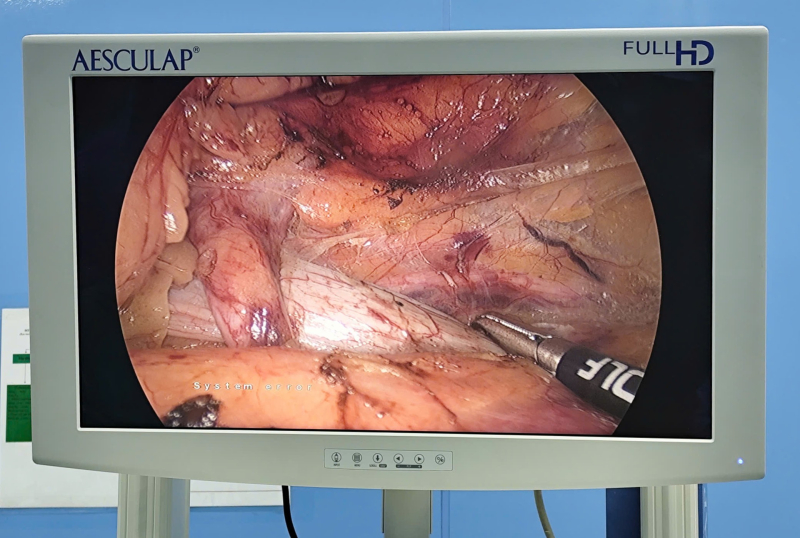

BSCKII Dương Xuân Hiệp cùng êkíp đang tiến hành phẫu thuật cho bệnh nhân.

khi hội chẩn chuyên môn, các bác sĩ chỉ định phẫu thuật nội soi ổ bụng chuyển vị niệu quản ra trước tĩnh mạch chủ dưới.

Quá trình phẫu thuật được thực hiện tỉ mỉ, khéo léo nhằm bóc tách an toàn hiệu quản, tránh tổn thương tĩnh mạch chủ và các cấu trúc lân cận. Đồng thời tiến

hành tán sỏi niệu quản trái, đặt sonde JJ 2 bên.

Sau gần 2 giờ, Kíp phẫu thuật do BSCKII Dương Xuân Hiệp, Trưởng khoa Ngoại tổng hợp, phụ trách phòng TCCB cùng ê kíp đã phẫu thuật thành công, niệu quản được tái tạo lưu thông tốt, chức năng thận được bảo tồn tối đa. Sau mổ, bệnh nhân hồi phục tốt, tiểu tiện bình thường.